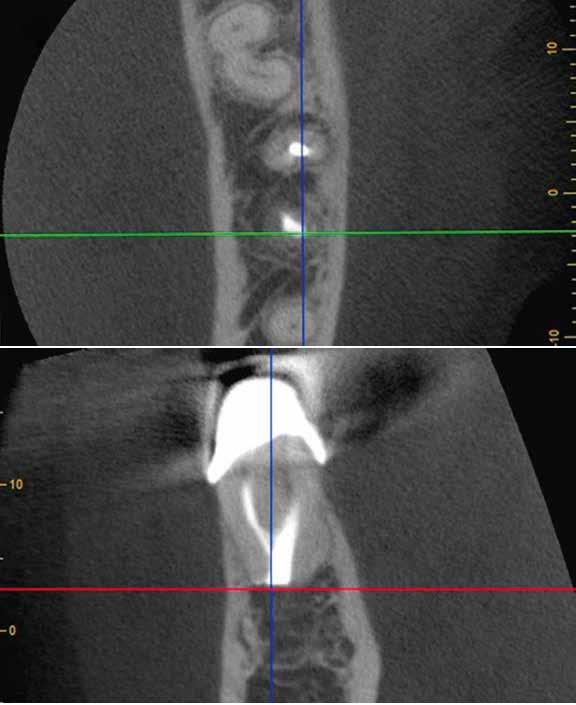

1. a–f ábrák: A cingulumon keresztül gömbfúróval kialakított hozzáférés a trepanációs kavitás labiális irányba történő túlzott mértékű kiterjesztését eredményezheti, és ez lényegesen növelheti a perforáció esélyét (a). A guttapercha átsejlik a lágyrészek alatt (b). Klinikailag igazolt perforáció (c). A preoperatív sagittális irányú CBCT-szeleten jól látható a labiális perforáció (d). Labiális irányú perforáció (fekete nyíl; e). A tényleges gyökércsatorna (piros nyíl; f).

5. a–l. ábrák: Az incisális élen keresztül kialakított hozzáférés lehetővé teszi a pericervikális dentin megőrzését. Kalcifikáció esetén CBCT-felvétel készítése hasznosnak bizonyulhat a hozzáférési nyílás tervezése során (a–d) . Minden fog koronai helyreállítása a gyökértömés elkészítésével egyidejűleg történt. A négyéves (e–h) és a kétéves (i–l) kontrollok alkalmával készített röntgenfelvételeken teljes gyógyulás látható. Mindkét fog tünetmentes és funkcióképes volt. (Dr. Viraj Vora esetei)

Szuvas lézión keresztül történő hozzáférés (a). A fog koronai helyreállítása a gyökértömés elkészítésével egyidejűleg történt (b és c). (Dr. Dale Jung esete)

kialakítása során fennáll a fog labiális irányú perforációjának veszélye, mivel ilyenkor a foganyag elvételét labiális irányú fúrótartással kezdjük. Nemrégiben újragondolták a

hozzáférési nyílás kialakítási protokollt, amelyet már ko

rábban, két endodonciai közleményben közzétettek. Ezekben a frontfogak hozzáférési nyílásainak kialakítását inci

sálisabb megközelítéssel javasolták. 21,22 Az új ajánlásban azt javasolják, hogy a frontfogakban történő hozzáférési nyílás kialakítását a cingulumtól távolabb, inkább az incizális él közelében kezdjük meg 19. Ez lehetővé teszi a lehető legtöbb pericervikális dentin megőrzését és kizárólag a legszükségesebb mennyiségű dentin kerül eltávolításra. Emellett ez a kialakítás a cingulumon keresztül történő hozzáféréshez képest egyenesebb hozzáférést biztosít a labiális és a linguális, vagy palatinális csatornákhoz, valamint lehetővé teszi a csatornák hatékonyabb tisztítását. 21 A fogak kopása esetén a hozzáférést az incisális „felszín” közepén alakítjuk ki (3. a-b ábrák) . A frontfogak kezelése során a megfelelő fúró kiválasztása is kiemelkedően fontos szereppel bír. A korábban ajánlott gömbfúrók használata ma már kifejezetten kontraindikáltnak számít. A gömbfúrók használatakor jellemzően egy fordított tölcsér alakú üreg kerül kialakításra. Ezekben az esetekben az üreg egyre szélesebb lesz, ahogy egyre mélyebbre hatolunk a fúrónkkal (2. a-b ábrák) 23 A gömbfúrók helyett olyan fúrók használata javasolt, amellyel elkerülhető lehet a trepanációs kavitás túlzott mértékű kiterjesztése, és amely segítségével a hozzáférési nyílás legszűkebb részét a pericer -

zésére. Ez azért fontos, mert a frontfogak funkcionális megterhelése során – a PCD-nek megfelelően elhelyezkedő területben – jelentős stressz ébred (5. a–l ábrák) 24 Szükség esetén egy CBCT-felvételt is készíthetünk. A 3D-s adatok jelentős mértékben segíthetik a klinikus munkáját a gyökércsatorna koronális vetületének vizualizálásában, és ennek alapján az egyenes vonalú hozzáférés biztosításához szükséges belépési pont meghatározásában (5.

a–l ábrák) . Ha a kofferdám izolálás a szomszédos fogakra is kiterjesztésre kerül, úgy a kezelést végző orvos sokkal magabiztosabban tudja a gyökerek angulációját vizualizálni (3. a-b ábrák)